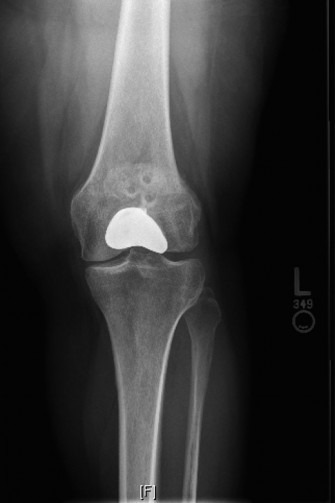

A 48-year-old woman presents to the emergency department complaining of acute left knee pain and inability to…

A 48-year-old female patient presents with anterior left knee pain. She has had a history of recurrent patell…